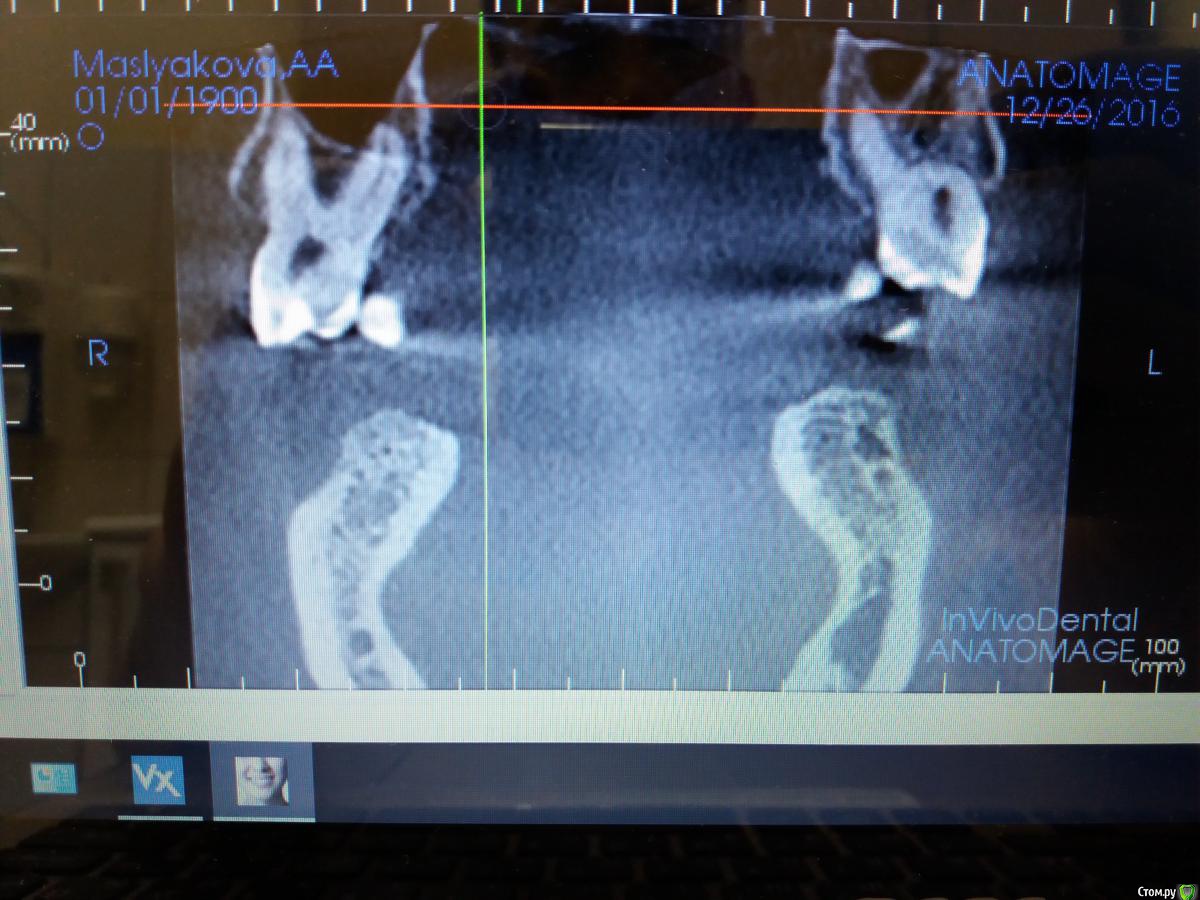

azerty Опубликовано 19 января, 2017 Поделиться Опубликовано 19 января, 2017 Что бы не плодить темы, подскажите коллеги,возможна ли интрузия моляров на верхней челюсти при очень близком расположении корней рядом с гайморовой пазухой?Не произойдет ли перфорация дна пазухи?Снимки прикреплю завтра,спасибо! Ссылка на комментарий

Opdihatop Опубликовано 22 января, 2017 Поделиться Опубликовано 22 января, 2017 Перфорации не будет скорее всего (особенно, если силы давать небольшие), но и интрузия идти будет очень медленно. Ссылка на комментарий

orthophil Опубликовано 6 февраля, 2017 Поделиться Опубликовано 6 февраля, 2017 Господа! О какой перфорации вообще идет речь. Моляры же не молотком вколачивать придется. А вот расстояние между верхушками и гайморовой пазухой уменьшится. Ссылка на комментарий